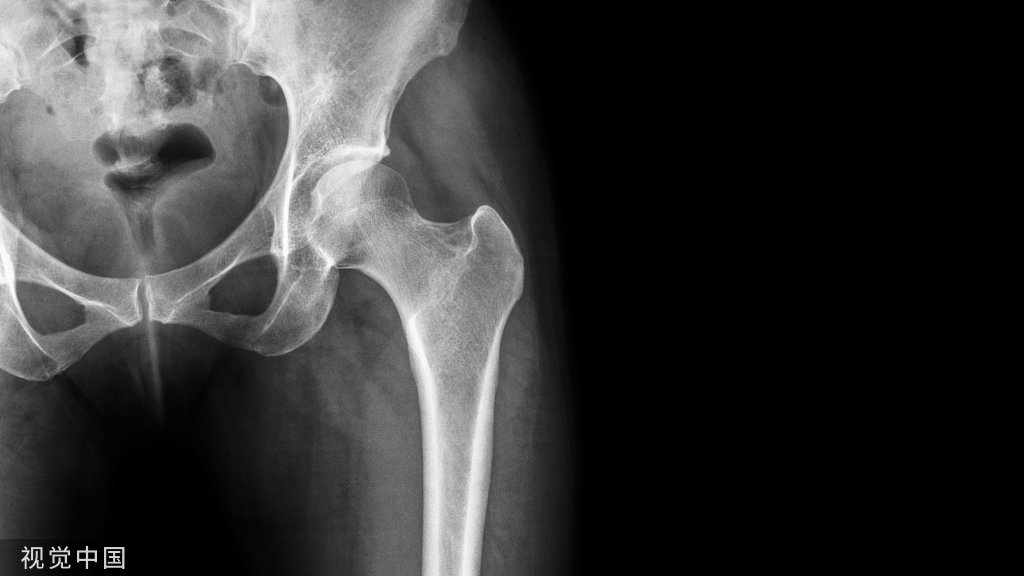

开放性骨折是创伤骨科治疗的难点,治疗效果取决于伤情严重程度、治疗方案,以及手术操作和护理。今天我们就来学习一下

开放性骨折是创伤骨科治疗的难点,治疗效果取决于伤情严重程度、治疗方案,以及手术操作和护理。最适合患者的治疗方案绝非某一单一因素所决定,需要多科室协作,在详细评估的基础上,在ERAS理念的指导下,结合实际情况,给予最合理、最可行的措施。开放性骨折的治疗效果虽然很大程度上取决于患者的伤情及自身情况,但绝大多数情况下通过全面的考量和对细节的把握,可以避免不必要的并发症。